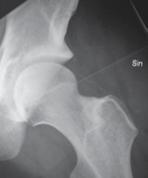

35 årig man som ådragit sig en skada av höger fot vid MC-olycka. Vid undersökning finner du att foten är svullen samt att det finns ett plantarhematom. Diffus ömhet över fot + fotled. Röntgen fotled ua. Röntgen fot: se bifogade bilder.

a. Vilken skada har inträffat? (1p)

b. Kompletterande utredning? (1p)

c. Behandling? (1p)

a. Hematomet i fotsulan och röntgenbilden talar för en allvarlig skada och att man bör misstänka en skada av Lisfrancs led. Denna

skada missas eller misstolkas ofta och ger obehandlad lätt upphov till bestående besvär.

b. Undersökningen bör kompletteras med CT.

c. Reposition och operativ fixation alternativt artrodes av skadade leder.